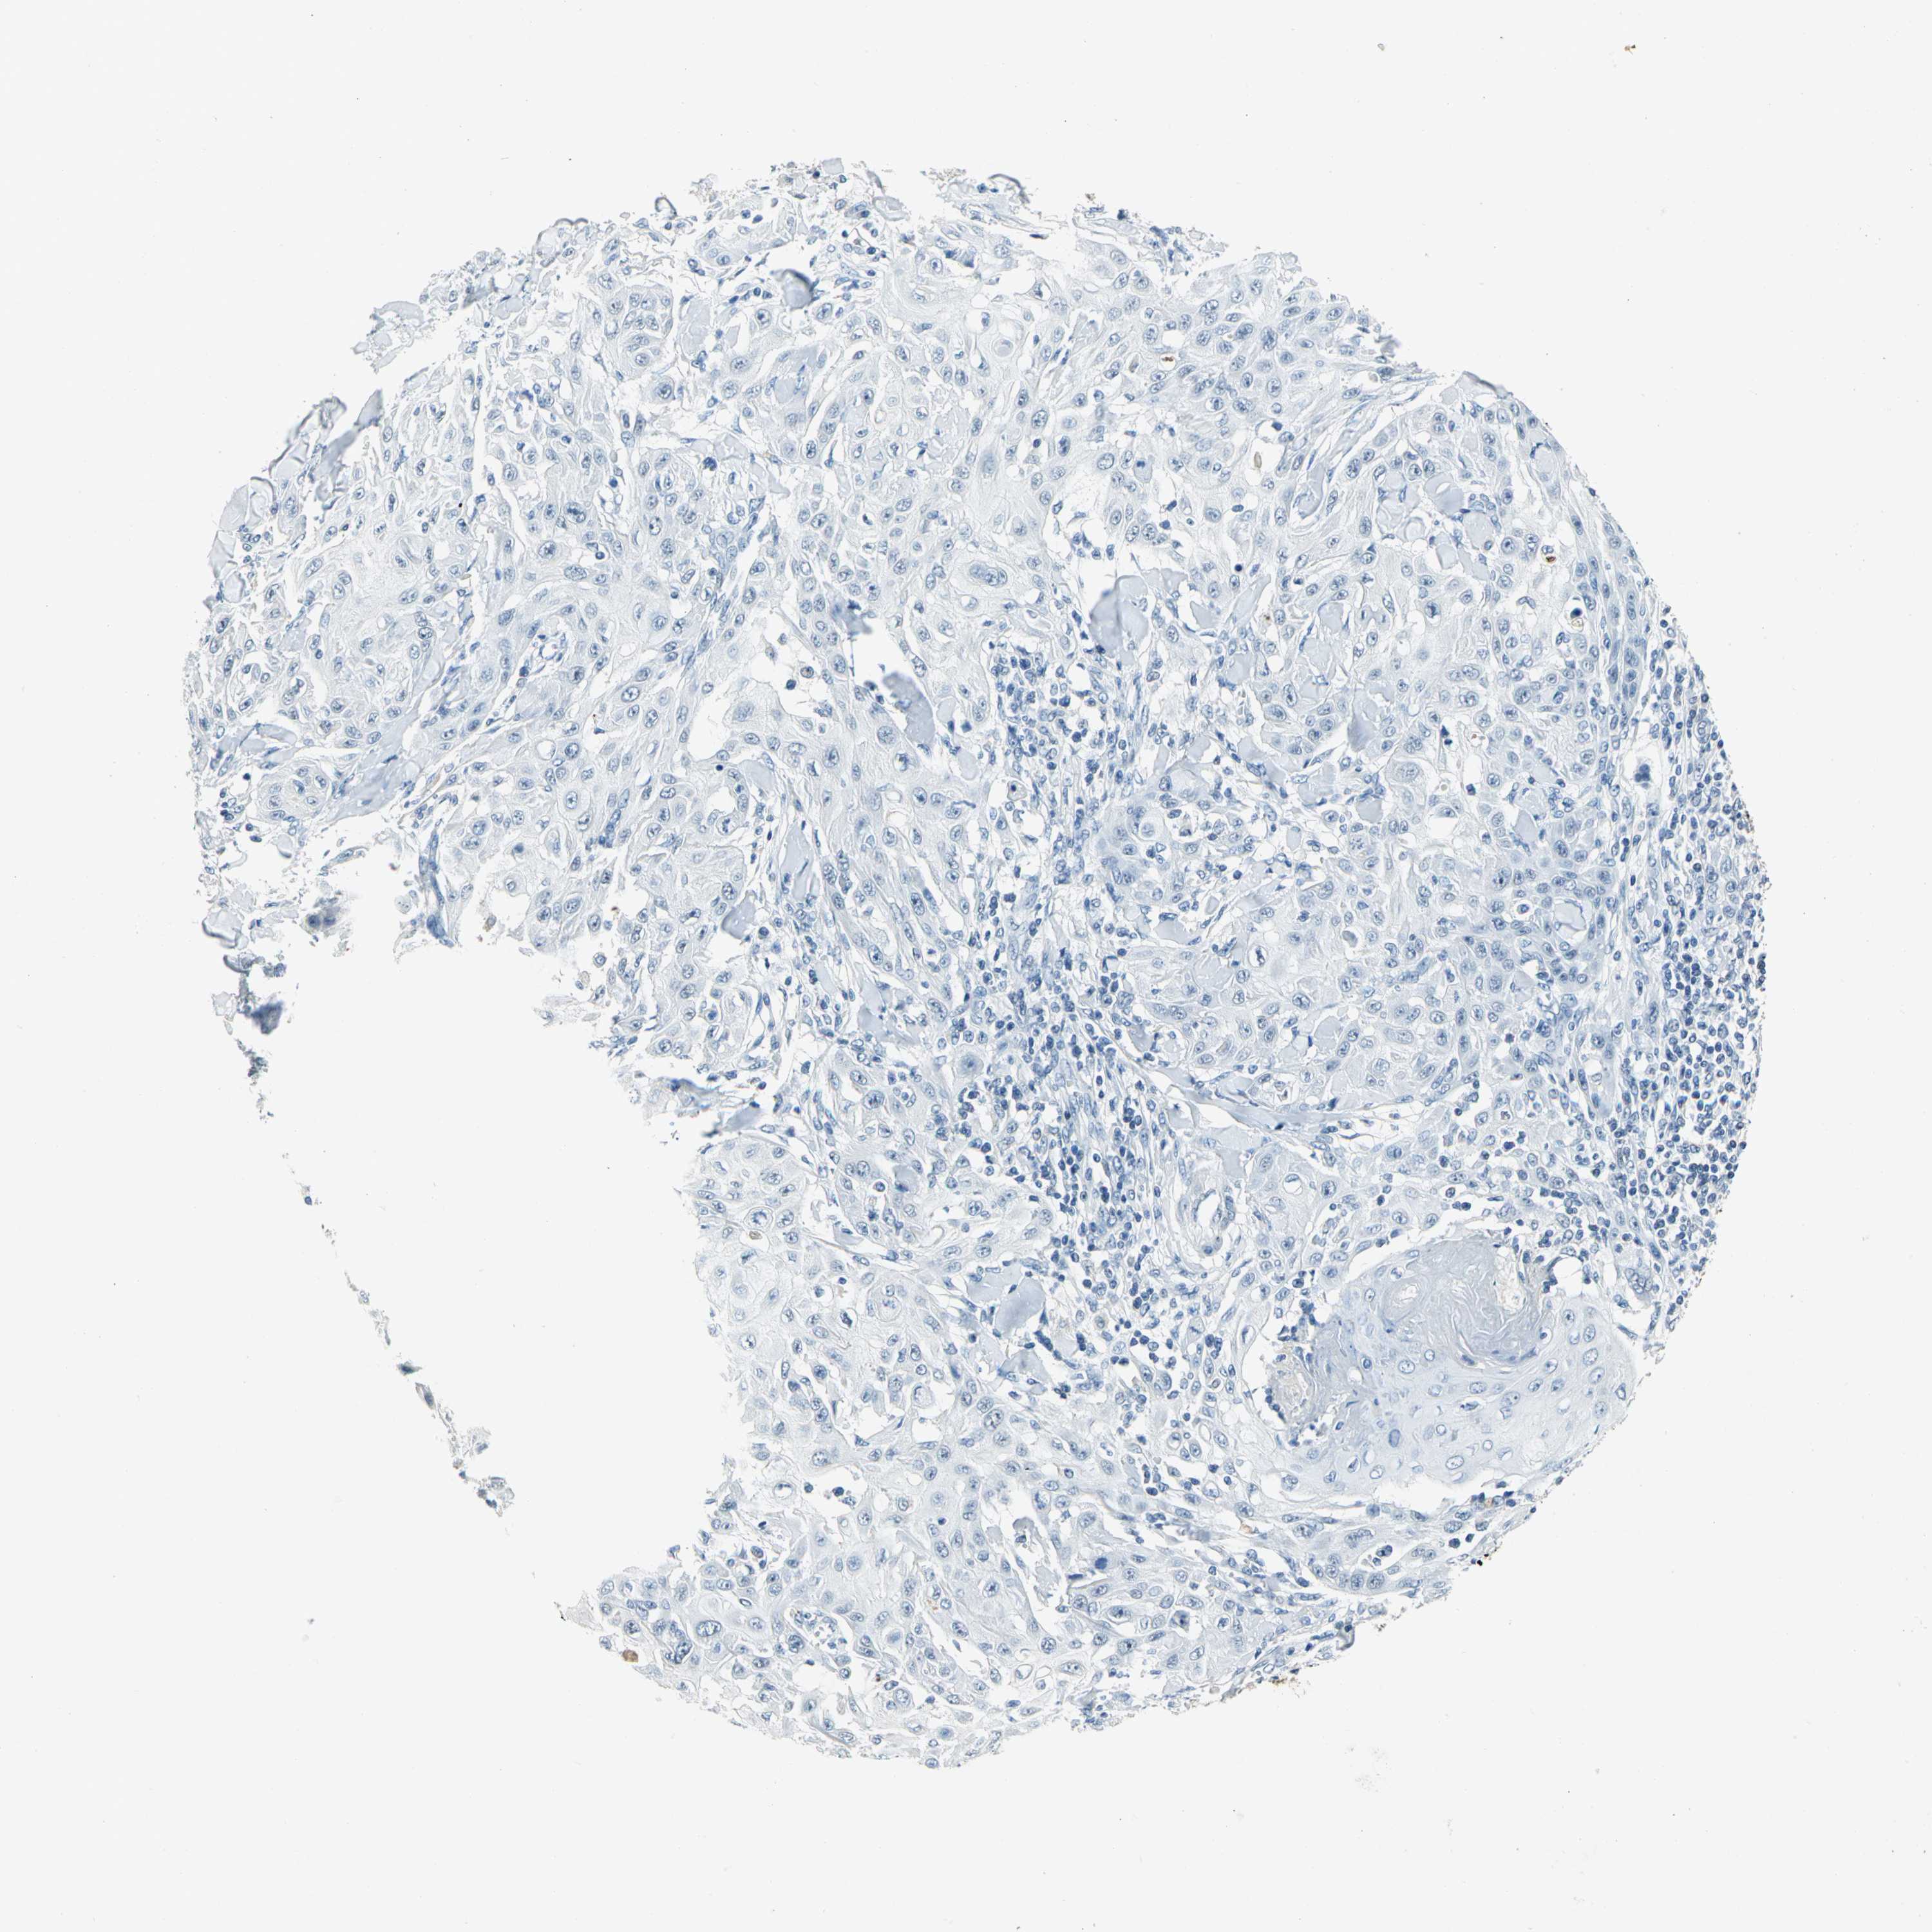

Basal cell and squamous cell cancer

SKIN CANCER - Protein expressioni

A mouse-over function shows sample information and annotation data. Click on an image to view it in a full screen mode. Samples can be filtered based on level of antibody staining by selecting one or several of the following categories: high, medium, low and not detected. The assay and annotation is described here.

Antibody stainingi

Antibody staining in the annotated cell types in the current human tissue is reported as not detected, low, medium, or high, based on conventional immunohistochemistry profiling in selected tissues. This score is based on the combination of the staining intensity and fraction of stained cells.

Each image is clickable and will lead to virtual microscopy that enables deeper exploration of all samples and also displays staining intensity scores, fraction scores and subcellular localization as well as patient and tissue information for each sample.

Antibody CAB004551

Staining

Not detected

Negative

None

Squamous cell carcinoma, NOS

Basal cell carcinoma